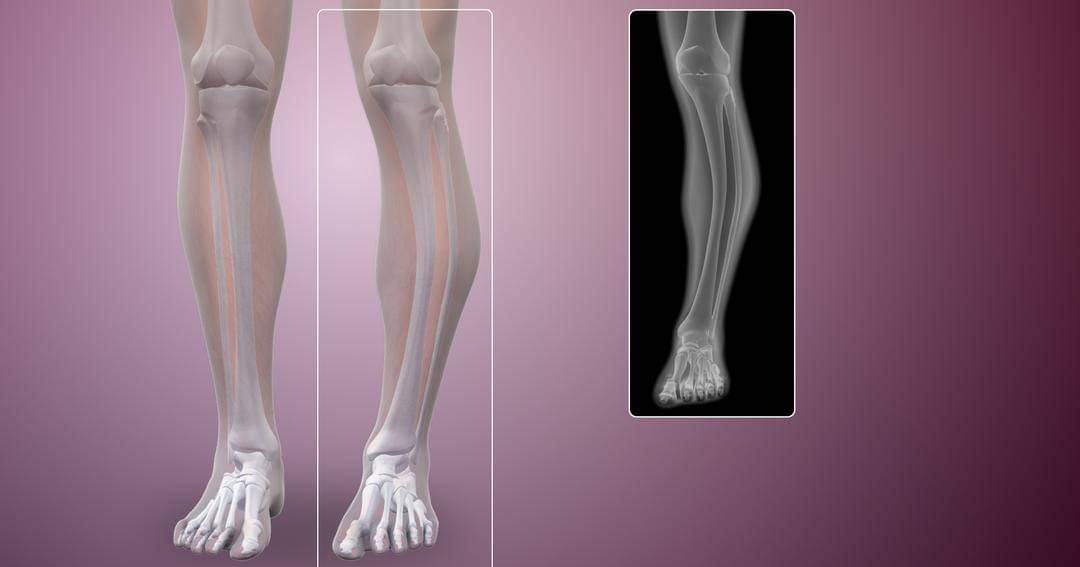

3. Skoliosis

Skoliosis adalah kelengkungan abnormal tulang belakang yang terbentuk seperti huruf S atau C. Gangguan ini sering terjadi pada percepatan pertumbuhan anak sebelum pubertas, dengan kasus biasanya didiagnosis dalam tujuh tahun pertama.

Pada sekitar 80 persen kasus skoliosis, tidak ada penyebab yang dapat diidentifikasi, meskipun hal itu dapat terjadi karena cacat lahir, kelainan neurologis, dan kondisi genetik.

Gejala skoliosis tergantung pada tingkat keparahan kondisinya, termasuk memiliki satu tulang belikat lebih tinggi atau lebih menonjol dari yang lain, pinggul tidak rata, tulang belakang berputar, masalah pernapasan, dan sakit punggung.